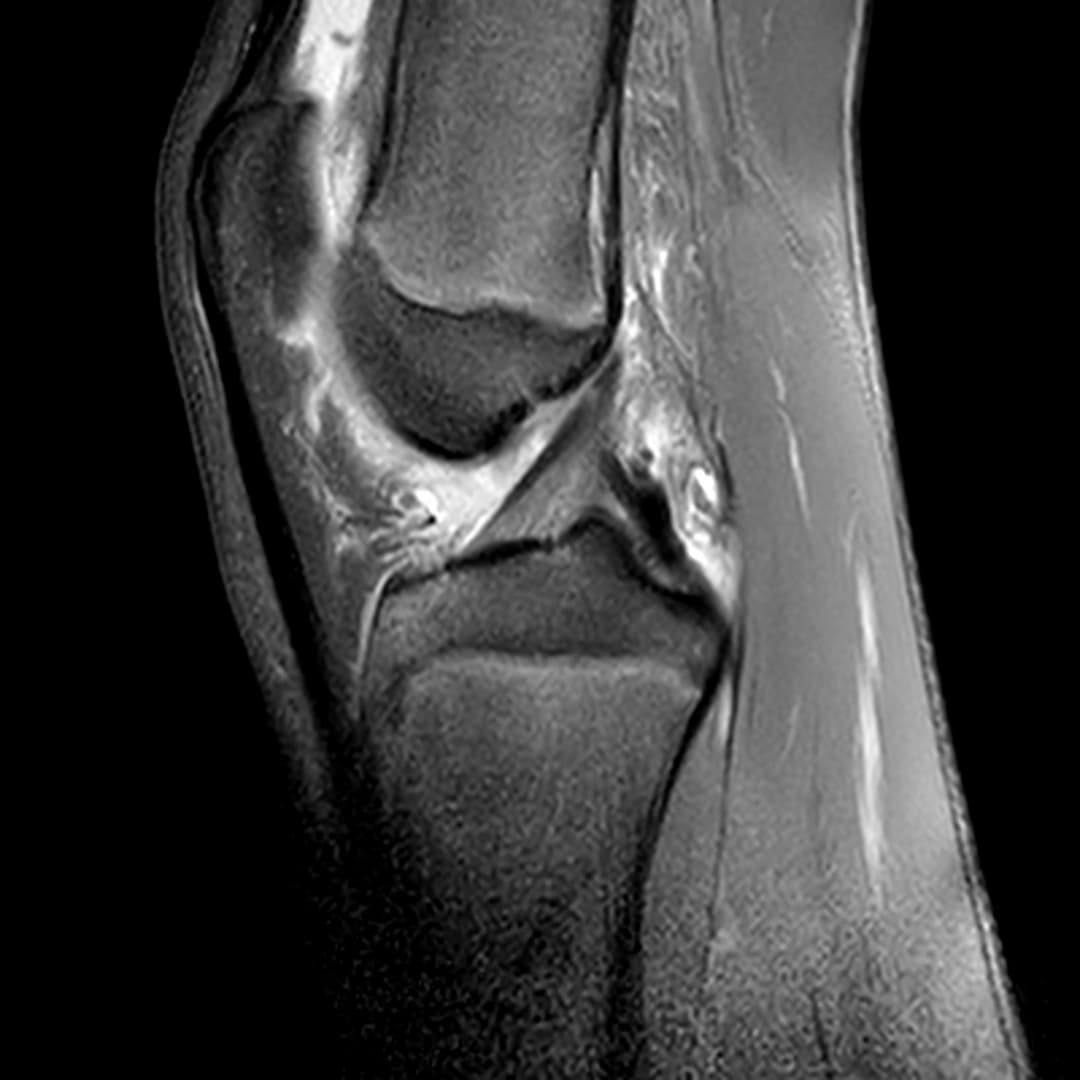

Contusion osteo-chondrale du genou

Présentation clinique

Douleurs post traumatique et gonflements

IRM

Intégrité ligamentaire et méniscale

Fracture sous chondrale par impaction avec œdème sous chondral en miroir du compartiment fémoro-tibial médial.

Epanchement articulaire abondant.